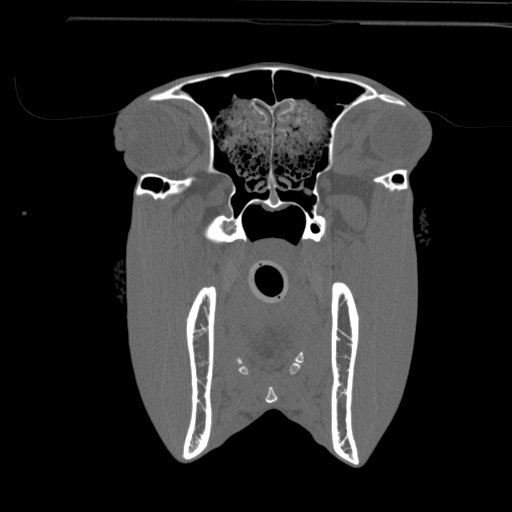

The modern Through-Silicon-Via (TSV) stacked CT detectors provide high-resolution images with low noise and high contrast, while the 40 cm gantry and 30 cm field-of-view provide additional space and information for your diagnostic needs versus VetTom 8.